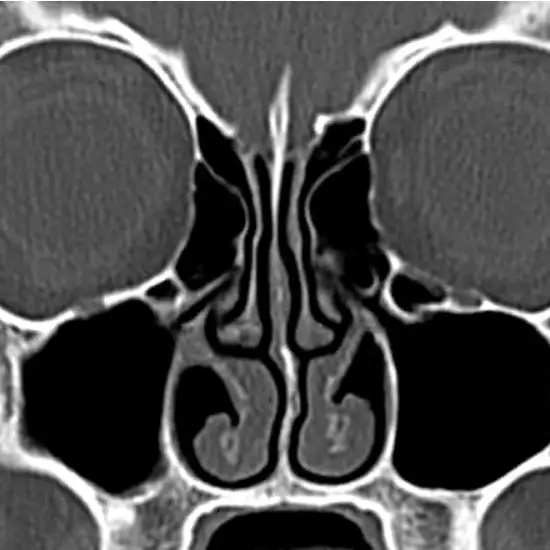

CECT Nose (Contrast- ContrastEnhanced computed Tomography of Nose) is an imaging procedure that uses an x-ray beam and contrast media to obtain images of the paranasal sinus. This scan is used to detect a variety of problems such as nasal polyps, fractures, inflammation, infection of the sinuses, fluid-filled sinuses, etc. For this scan, the radiologist will inject contrast material into the vein in the arm.